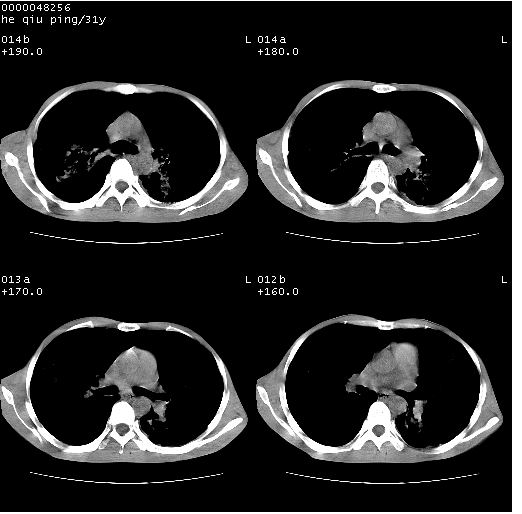

标题: CT13402:M,31Y。肺结核伴空洞形成? [打印本页]

标题: CT13402:M,31Y。肺结核伴空洞形成?

咳嗽半月余,消瘦体质,呼吸音弱。无其他病史。cr:肺转移瘤待。

双上肺多发空洞,双飞散在分布大小不一的片状结高密度影节状大片状高密度影。符合结合肉芽肿形成及空洞形成。

双侧弥漫性病变,双上叶尖后段、下叶北段见多个空洞,多见于结核感染。右中叶及双下叶斑片状,结节状影,考虑为肉芽肿形成及支气管播散。但由于患者消瘦体质,抵抗力低下,若继发感染,如金葡菌肺炎也有可能。

病灶多形性,有空洞形成。考虑肺结核伴空洞形成,两下肺支气管播散!